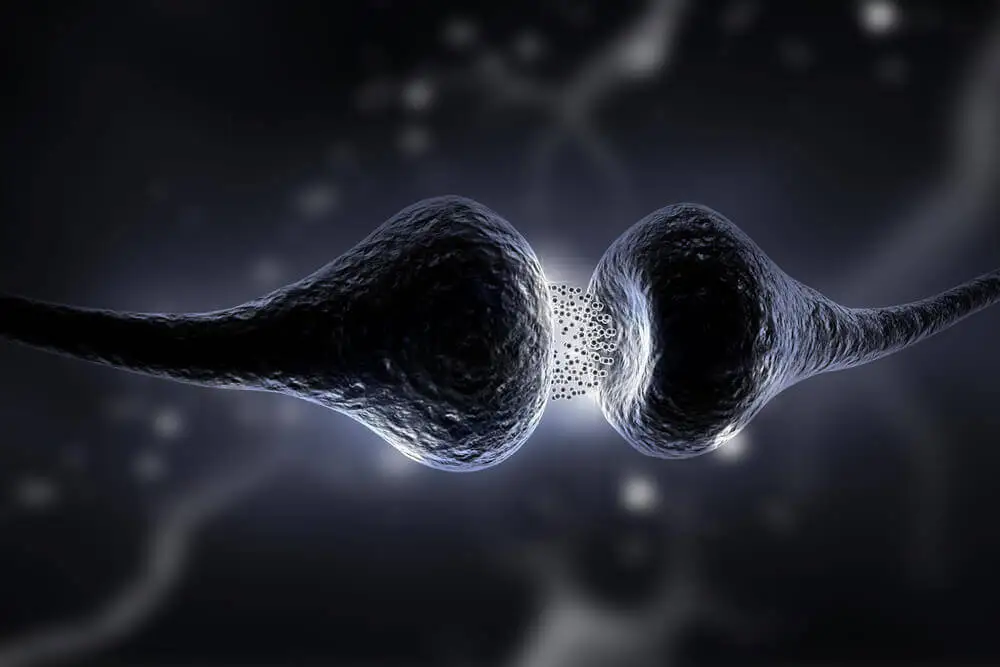

La sinapsis es la zona donde se comunican las neuronas entre sí. Cuando nacemos, el número de sinapsis de las neuronas de la corteza cerebral es limitado. Se estima que son unas 2500 sinapsis. Sin embargo, a medida que pasan los años, este número aumenta casi a 10.000 sinapsis por neurona.

Esto sucede porque, a medida que crecemos, vamos experimentando y aprendiendo diferentes conductas. Todo esto provoca que se creen nuevas conexiones neuronales y también que se fortalezcan. No obstante, también conlleva que las que no se usan se eliminen o mueran.

Lo que ocurre con el proceso de neuroplasticidad es que se estimula que se creen o se regeneren más sinapsis durante toda la vida. Sucede mediante diferentes mecanismos moleculares y químicos.

Por ello, cada vez que adquirimos nuevos conocimientos, las sinapsis se ven reforzadas o aumentadas. Los mecanismos más importantes por los que funciona la neuroplasticidad son: